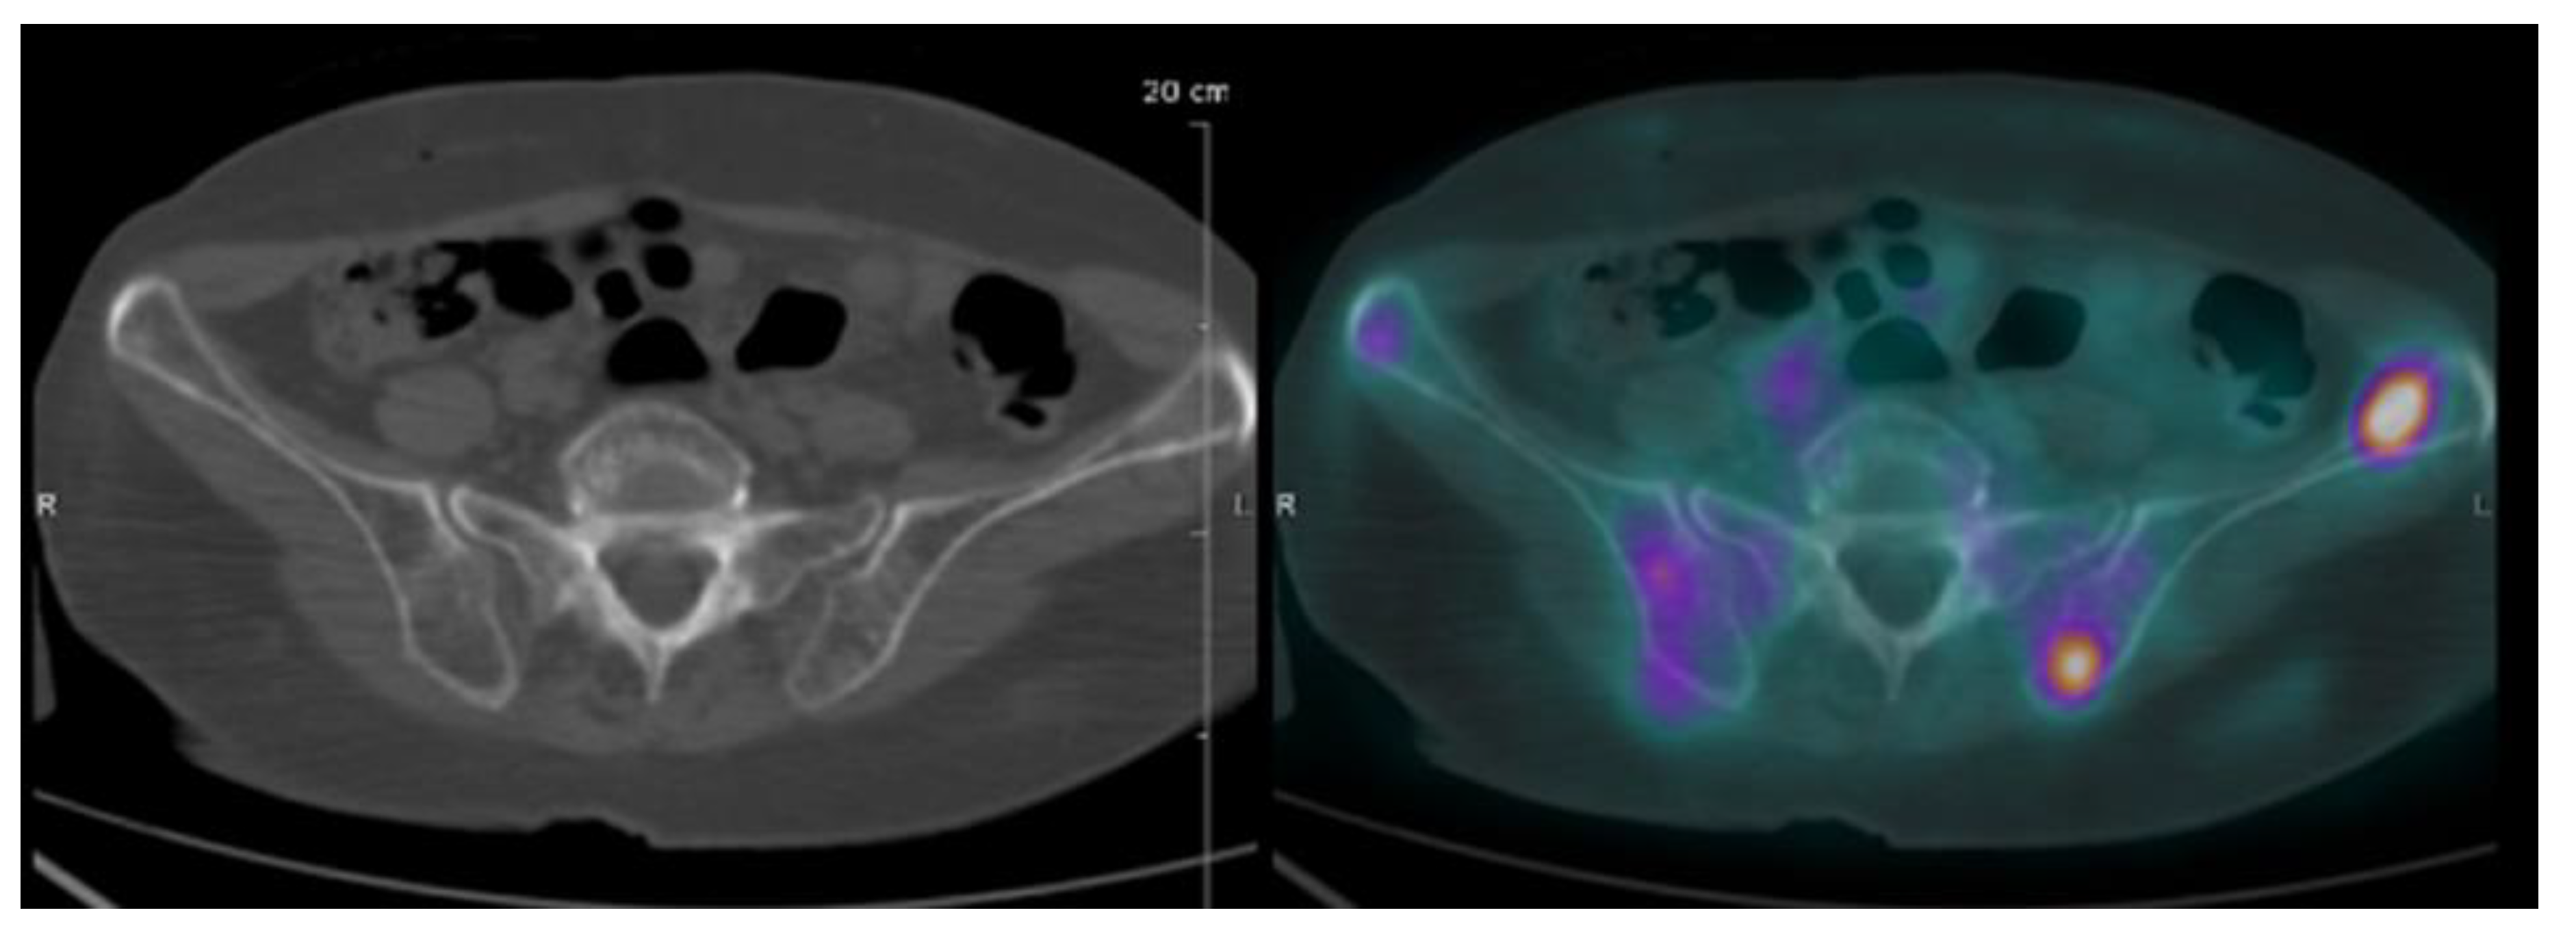

| Focal lesion | Foci of uptake above the surrounding background noise on two successive sections with or without osteolysis on the CT image | Suggested as pejorative prognostic biomarker using cut off 3. | Bartel et al., 2009 [8] |

| EMD | Tissue invasion without contiguous bone involvement. | Presence of EMD suggested as pejorative prognostic biomarker | Zamagni et al., 2011 [9] |

| PMD | Soft tissue invasion with contiguous bone involvement. | Presence of PMD suggested as pejorative prognostic biomarker | Moreau et al., 2019 [19] |

| Diffuse medullary involvement | Homogenous diffuse uptake of the pelvic-spinal-peripheral skeleton higher than the liver background. | Prognostic value currently not demonstrated | |

| FDG-PET/CT abnormality | Presence of Focal lesion(s) and/or EMD lesion(s) and/or PMD lesion(s) and/or diffuse medullary involvement. | Absence of FDG-PET/CT abnormality considered as a favourable prognostic | Rasche et al., 2017 [16] |